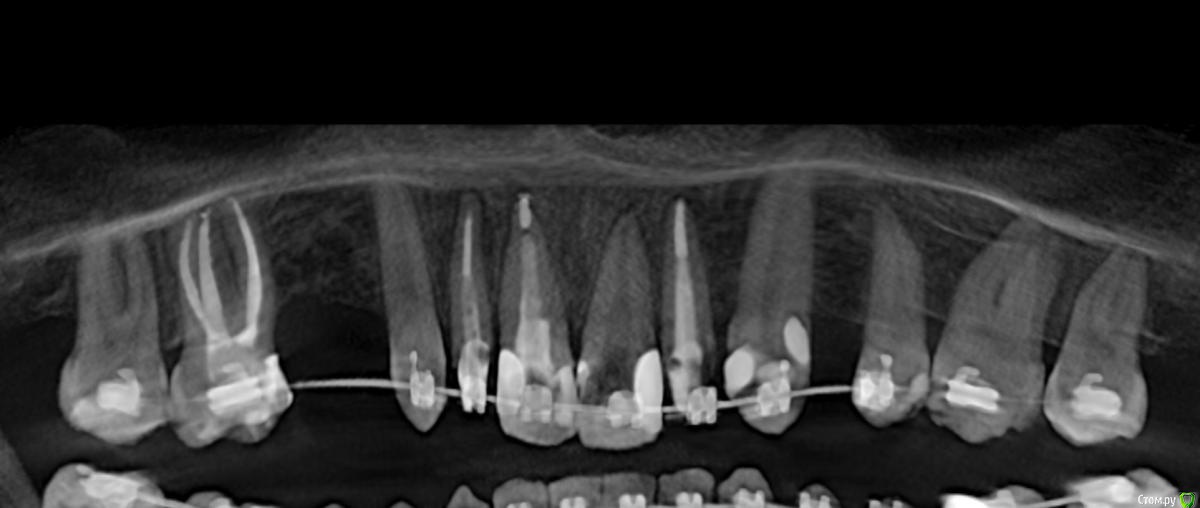

Al..ks Опубликовано 18 апреля, 2019 Поделиться Опубликовано 18 апреля, 2019 Добрый день. Планируется имплантация(15 или 14. брекеты ношу, поэтому не знаю какой будет)+аугментация (в области кармана 17 и при имплантации в случае недостатка кости)+пластика десны+установка формирователя. Все за раз.На выбор dentium, Astra, Nobel, Straumann. Подходят любые и выбор за мной(я склоняюсь к Астре). Правильный выбор? . Плюс ко всему по КТ там отсутствует кортикальный слой( по словам врача) я так понял с наружней стороны, поможет ли аугментация?И поможет ли она с карманом 17? И так как двигали зубы в области корня 11 появилась пустота (толи уже было)в середине лечения и на данный момент Надо ли делать резекцию корня - или канал перелечивать (там ставили СВШ перед брекетами) перед протезирование? Ссылка на комментарий

suballex Опубликовано 19 апреля, 2019 Поделиться Опубликовано 19 апреля, 2019 Добрый день. Планируется имплантация(15 или 14. брекеты ношу, поэтому не знаю какой будет)+аугментация (в области кармана 17 и при имплантации в случае недостатка кости)+пластика десны+установка формирователя. Все за раз.На выбор dentium, Astra, Nobel, Straumann. Подходят любые и выбор за мной(я склоняюсь к Астре). Правильный выбор?Правильный Плюс ко всему по КТ там отсутствует кортикальный слой( по словам врача) я так понял с наружней стороны, поможет ли аугментация?И поможет ли она с карманом 17?Аугментация с карманом не поможет. В остальном - да И так как двигали зубы в области корня 11 появилась пустота (толи уже было)в середине леченияи на данный момент Надо ли делать резекцию корня - или канал перелечивать (там ставили СВШ перед брекетами) перед протезирование?Нужно сравнить КТ начала лечения и последнее. Рентгенологически, канал 11 пролечен хорошо. Возможно, это остаточные явления. Ссылка на комментарий